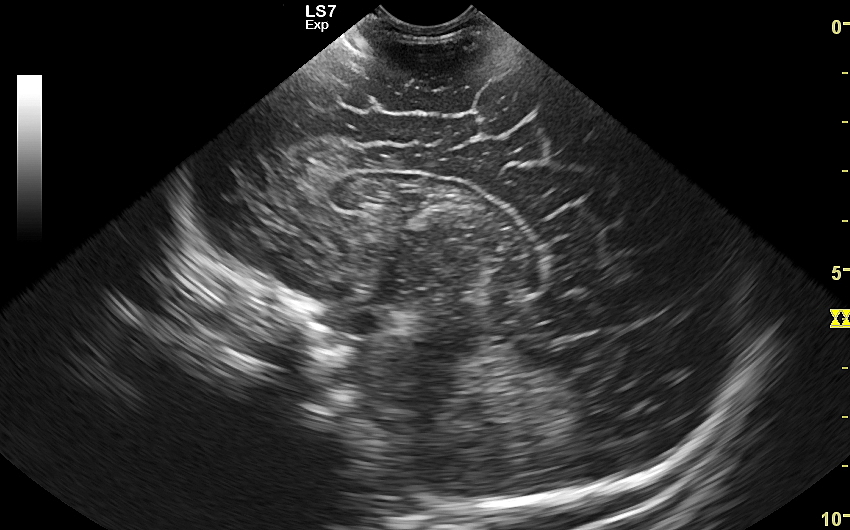

USG główki to podstawowa metoda diagnostyczna mózgu i struktur okołomózgowych u wcześniaków, noworodków i niemowląt. Badanie jest bezbolesne i nieryzykowne w porównaniu do rezonansu magnetycznego, podczas którego dziecko poddawane jest znieczuleniu ogólnemu. Przeprowadzenie szerokiego i szczegółowego badania USG główki jest możliwe aż do momentu zarośnięcia ciemiączka, czyli chrzęstnej struktury w pokrywie czaszki. Ze względu na cienką kość skroniową czaszki dziecka w późniejszym okresie możliwa jest wciąż częściowa ocena mózgowia w badaniu USG. Ambulatoryjne badanie USG przezciemiączkowe zwykle zalecane jest przez neonatologa, pediatrę lub neurologa dziecięcego w celu oceny mózgu wcześniaków, dzieci z małą masą urodzeniową, dzieci po epizodzie niedotlenienia lub krwawienia wewnątrzczaszkowego w trakcie porodu lub okresu noworodkowego, a także w przypadku wystąpienia drgawek, podejrzenia wady układu nerwowego, np. wodogłowia.

W USG główki dziecka oceniane są struktury wewnątrzczaszkowe, tj. mózg wraz z jego układem komór wewnętrznych, sploty naczyniówkowe, istota biała mózgu i obszary jąder podstawy mózgu, morfologia zakrętów i bruzd mózgowia, przestrzeń przymózgowa, a w trybach dopplerowskich wybrane naczynia tętnicze i żylne mózgu, w tym zatoki żylne. Oceniane są również cechy ciśnienia śródczaszkowego. W opisie badania podawane są również wymagane przez neurologa tzw. wskaźniki komorowe oraz wymiary wybranych struktur.

Badanie USG służy również ocenie dojrzałości mózgowia dziecka; otóż mózg wcześniaka różni się od mózgu starszego niemowlęcia. U tego pierwszego obserwuje się m. in. mniej zaawansowane bruzdowanie kory mózgowej oraz warianty rozwojowe, z których najczęstszym jest jama przegrody przezroczystej. Zaburzenia rozwoju kory mózgowej u płodu, a potem u niemowlęcia, obserwowane są w przypadku palenia papierosów przez ciężarną lub spożywania przez nią alkoholu, w przypadku powikłań przebiegu ciąży, a także powikłań okołoporodowych.